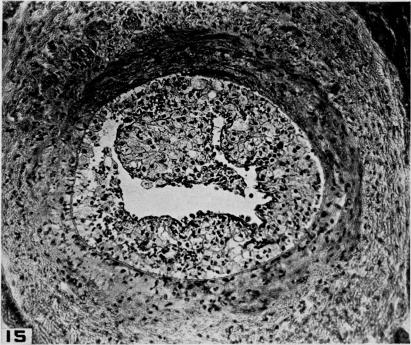

Studies on the pathogenesis of vascular disease; the effect of intravenous egg-yolk emulsions on inflammatory lesions of the aorta and coronary arteries of dogs.

Yale J Biol Med. 1956 Sep;29(1):9-22.